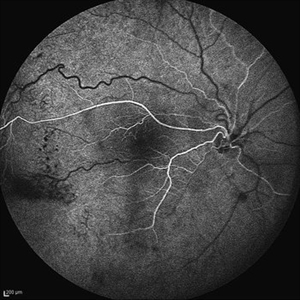

Behcet's Disease Behcet's DiseaseMar 13 2013 by Hamid Ahmadieh, MD Early phase FA of the left eye of a 23-year-old man with retinal vasculitis due to Behcet's disease . Photographer: Solmaz Shahmohammad, Negah Eye Center, Tehran Imaging device: Heidelberg Spectralis Condition/keywords: retinal vasculitis